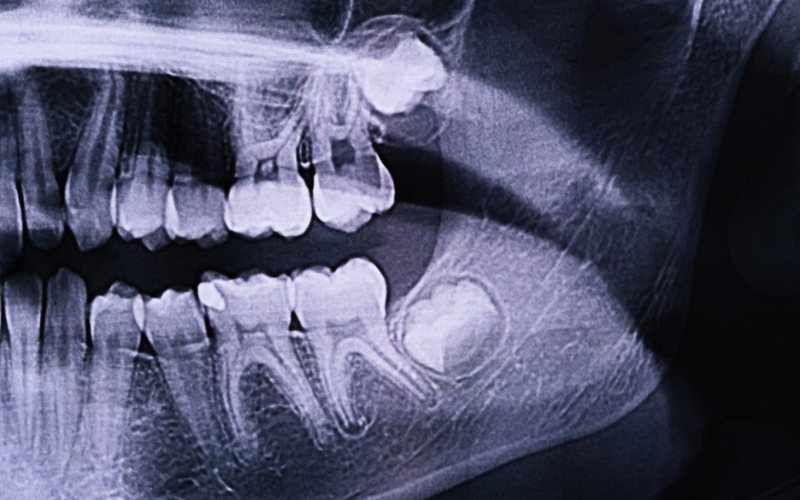

Supernumerary teeth are very rare, occurring in only a small percentage of the population. Oral Surgeons often use X-rays to identify these extra teeth during routine dental exams. However, if anyone experiences unusual symptoms or suspects the emergence of a new tooth after wisdom teeth removal, it’s essential to consult an oral surgeon promptly. Early detection and intervention can prevent potential complications and ensure proper dental care. So, don’t hesitate to schedule a visit to your oral surgeon for peace of mind and appropriate guidance.